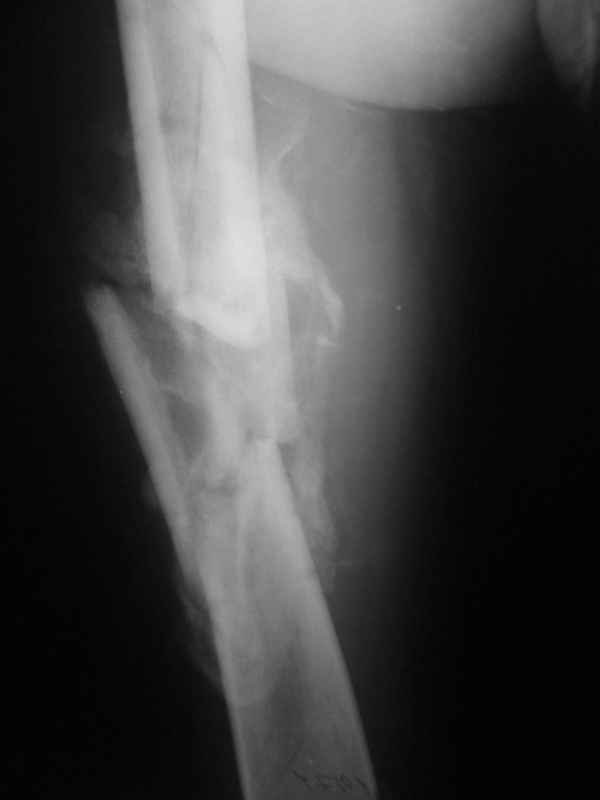

Re: Неправильно срастающийся оскольчатый перелом бедра

Конечно, снимки для планирования надо нормальные, не такой огрызок.

Можно закрыто мобилизовать отломки, наложить дистракционный аппарат, восстановить ось и длину, да и заштифтовать, на всякий случай с антибиотиковым цементным покрытием.

Вы думаете, что в данной ситуации возможна закрытая мобилизация?

Попробовать-то можно. И просто руками "об колено", а то и наложить аппарат, приложить флексионные и ротационые усилия прямо за разъединенные секции.

Если уж никак, то сделать чрескожную остеотомию.

Но если картинки недавние, IMHO должно получиться закрыто разобщить.